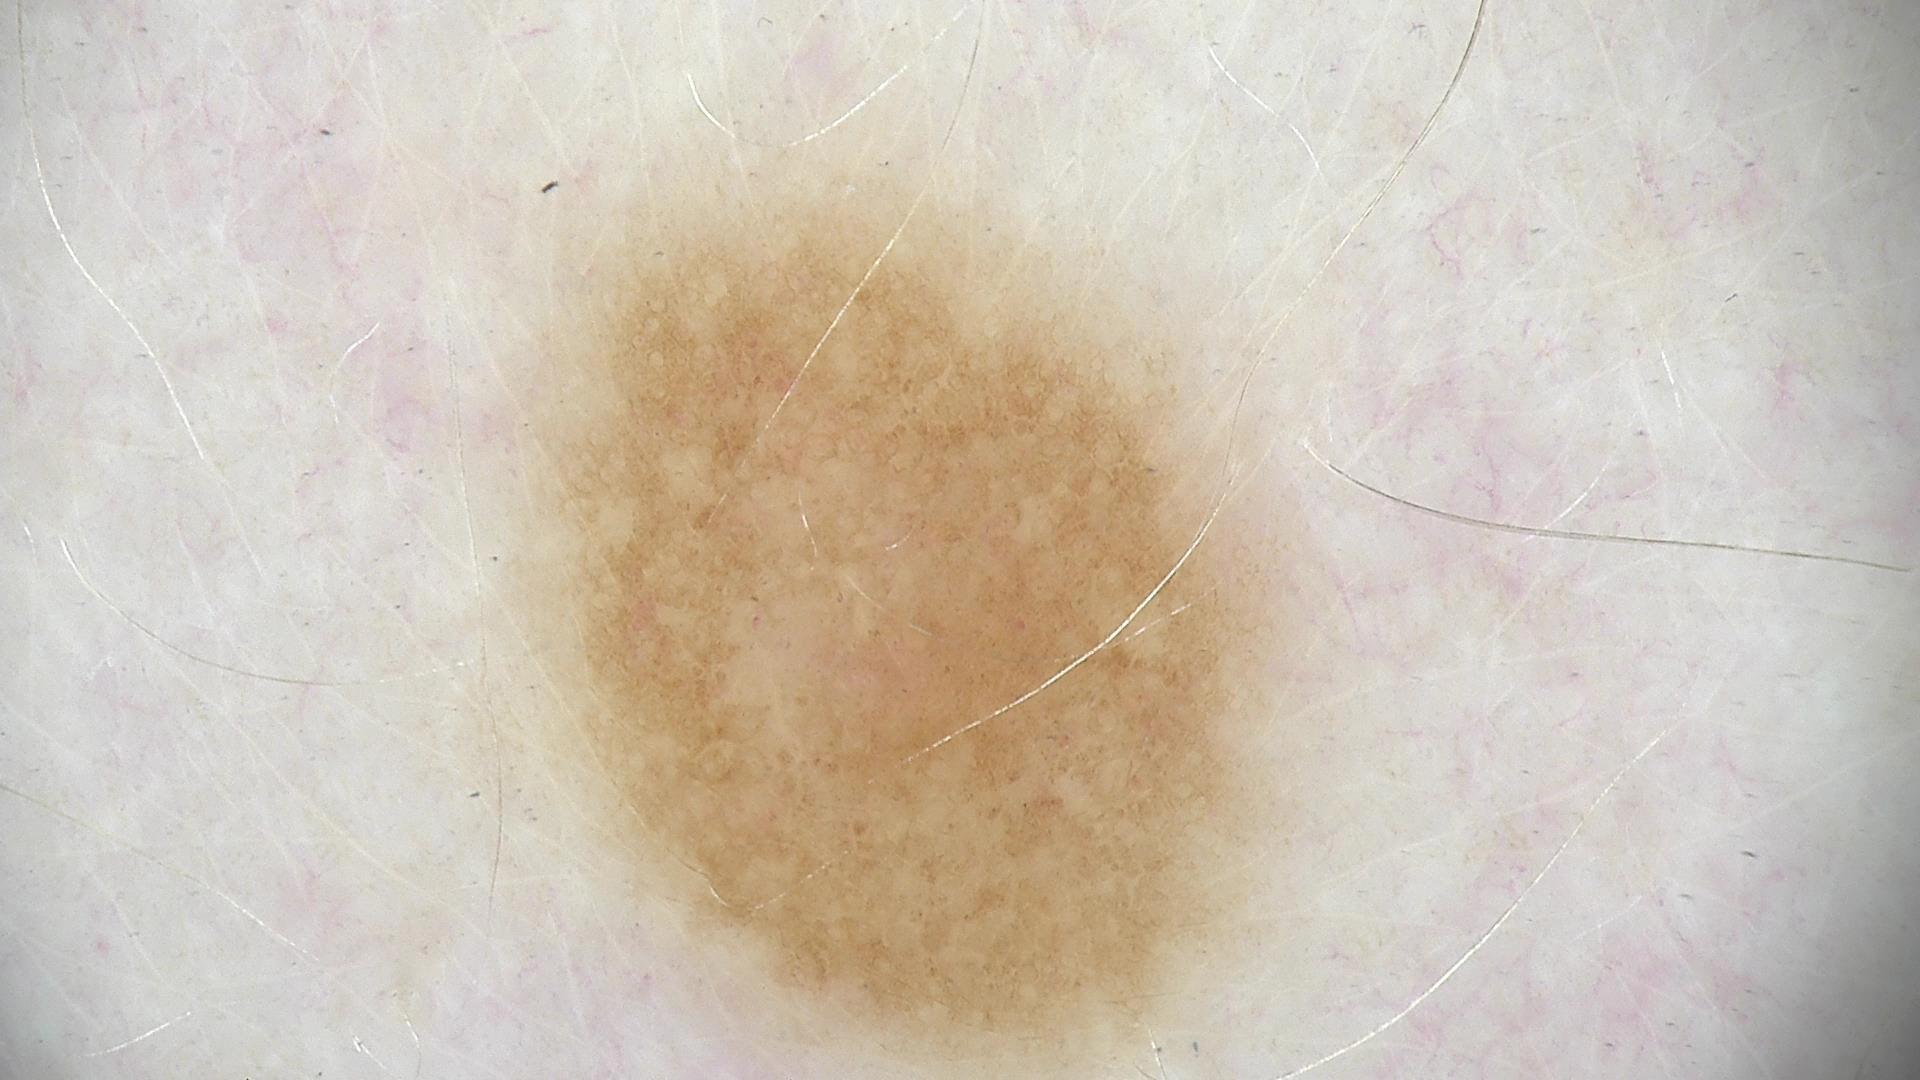

Skin lesion datasets provide essential information for understanding various skin conditions and developing effective diagnostic tools. They aid the artificial intelligence-based early detection of skin cancer, facilitate treatment planning, and contribute to medical education and research. Published large datasets have partially coverage the subclassifications of the skin lesions. This limitation highlights the need for more expansive and varied datasets to reduce false predictions and help improve the failure analysis for skin lesions. This study presents a diverse dataset comprising 12,345 dermatoscopic images with 40 subclasses of skin lesions, collected in Turkiye, which comprises different skin types in the transition zone between Europe and Asia. Each subgroup contains high-resolution images and expert annotations, providing a strong and reliable basis for future research. The detailed analysis of each subgroup provided in this study facilitates targeted research endeavors and enhances the depth of understanding regarding the skin lesions. This dataset distinguishes itself through a diverse structure with its 5 super classes, 15 main classes, 40 subclasses and 12,345 high-resolution dermatoscopic images.